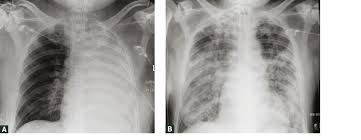

While some infections are subclinical, others result in localized acute or chronic disease, or fatal septicemia. Melioidosis infectionscan present like an infected wound, with swelling or ulcers at the exposure site, but they can also occur in the lungs, the bloodstream or widely spread throughout the body. Melioidosis is an often fatal infectious disease caused by the environmental bacterium, burkholderia pseudomallei.melioidosis is often misdiagnosed because it causes wide range of symptoms which often mimic those of other tropical diseases. It stems from bacteria found in contaminated water and. Melioidosis is an infectious disease caused by the bacteria burkholderia pseudomallei which is found in contaminated water and soil. An accurate map defining the global distribution of b. Because it can affect almost any organ, melioidosis can mimic many other diseases; Melioidosis, also known as whitmore's disease, is a bacterial infection that can affect both people and animals. Melioidosis is predominantly a disease of tropical climates and is spread to humans and animals through direct contact with the contaminated source. Melioidosis infection commonly involves the lungs. What are the symptoms of melioidosis? Melioidosis is a disease caused by bacteria called burkholderia pseudomallei. Melioidosis treatment usually starts with an iv antimicrobial infusion that lasts for a minimum of two weeks, the cdc says.

Pseudomallei from any clinical specimen is considered diagnostic for melioidosis. It is predominately a disease of tropical climates, especially in southeast asia and northern australia where it is widespread. Because it can affect almost any organ, melioidosis can mimic many other diseases; What are the symptoms of melioidosis? The disease occurs mostly in tropical areas of the world, primarily southeast asia and northern parts of australia. Melioidosis infection commonly involves the lungs. Melioidosis is potentially preventable, but there is a striking lack of evidence on which to base an effective prevention programme. Melioidosis is a bacterial disease that affects humans and many species of animals.